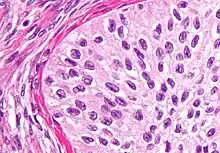

| High magnification micrograph of a Brenner tumor, a type of surface epithelial-stromal tumor. H&E stain. | |

Brenner tumors are uncommon surface-epithelial stromal cell tumors in which the epithelial cell (which defines these tumors) is a transitional cell. These are similar in appearance to bladder epithelia. The tumors may be very small to very large, and may be solid or cystic. Histologically, the tumor consists of nests of the aforementioned transitional cells within surrounding tissue that resembles normal ovary. Brenner tumors may be benign or malignant, depending on whether the tumor cells invade the surrounding tissue.